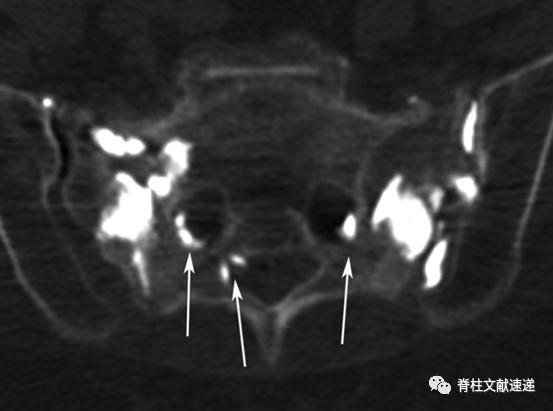

文献中描述了两例骶骨成形术相关骨水泥渗入神经孔的病例,如下图。有一过性 S1 神经炎,在经椎间孔硬膜外注射类固醇后消退。